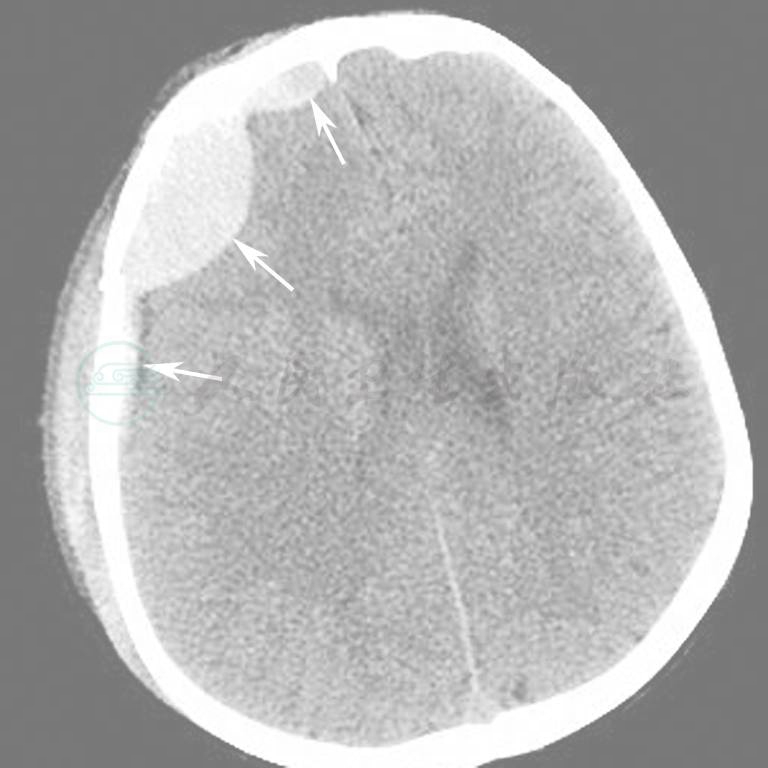

图15为颅脑外伤出血伴骨折病例。

图15  外伤后颅内出血(箭)

A.脑组织窗;B.骨窗;C.VR重建